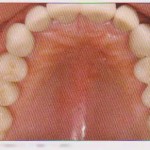

Пациентка 64 лет обратилась в клинику для изготовления несъемного протеза с левой стороны верхней челюсти. Соматическое состояние без особенностей. Пациентка не курила, не имела аллергии и не принимала лекарственных препаратов. Основная жалоба связана с нарушением жевания с левой стороны, где были утрачены зубы 25, 26 и 27. Антагонисты утраченных зубов находились в удовлетворительном состоянии.